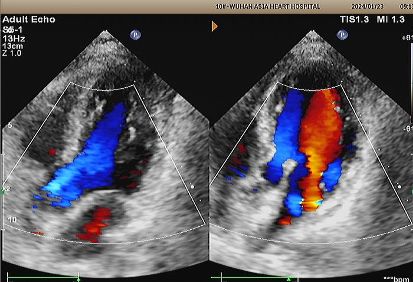

Gema 1 tahun:

No visible disc structures – replaced by 8mm tissue thickening at the septal implant site.

Zero residual shunt (rest or post-Valsalva).

Penyerapan perangkat lengkap dikonfirmasi.